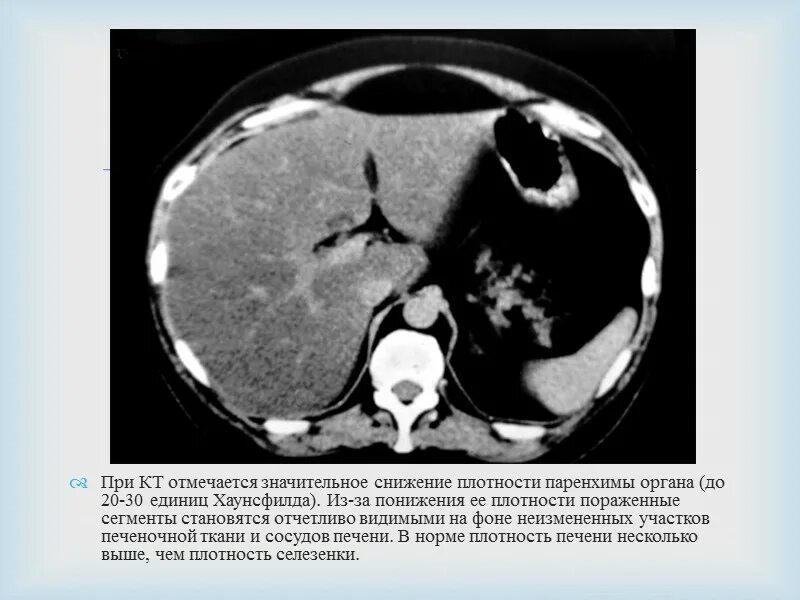

Паренхима печени диффузно снижена